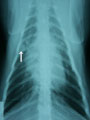

呼吸器 13-a 脂質性肺炎の猫の1例

雑種猫、オス、14歳。体重4.72kg。2ヶ月前に頭部腫瘍切除術前の胸部レントゲンで右肺前葉の領域に直径8mmの結節影があったが消失しないので腫瘍の可能性あり、肺葉切除することになった。

胸部レントゲン。